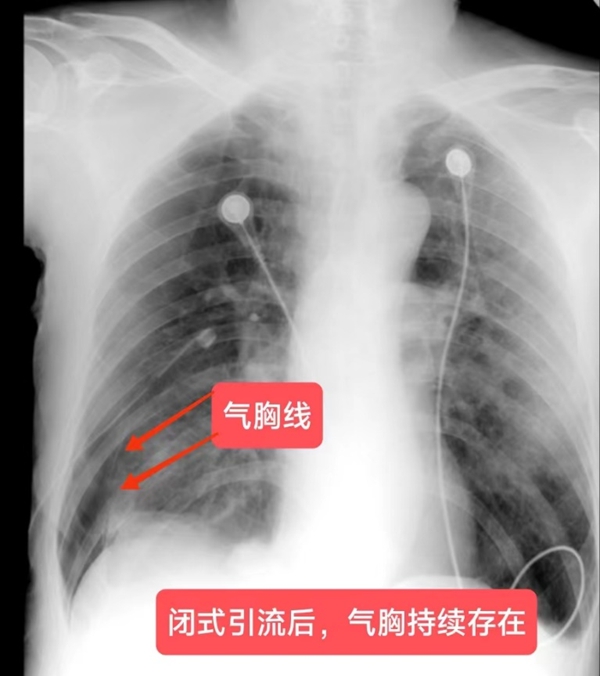

湖南日报·新湖南客户端(通讯员 刘福芝 刘嘉)70岁的彭爷爷患有慢性阻塞性肺疾病和双侧多发肺大疱,气胸反复发作。近日,彭爷爷再次因气促不适被120紧急送至娄星区人民医院(妇幼保健院),急查胸片显示右侧气胸(压缩45%),立即入住呼吸与危重症医学科并紧急给予实施“右侧胸腔闭式引流术”,经治疗,症状有所缓解。但10天后,彭爷爷身上的水封瓶内仍有气泡溢出,提示肺部存在持续漏气,被诊断为“难治性气胸”。

面对这一难题,呼吸与危重症医学科主任李儒鹏在详细了解彭爷爷的病情后,考虑其年纪大,肺功能很差,难以耐受外科手术治疗,于是提出了一种创新的治疗方法——化学性胸膜固定术。患者及其家属详细了解该治疗方案后,表示同意行化学胸膜固定术治疗难治性气胸。于是,在李儒鹏指导下,主治医生刘铁强为彭爷爷经胸腔闭式引流管注入了多西环素行化学胸膜固定术。经治疗,彭爷爷胸腔引流管连接水封瓶内的气泡逐渐减少,复查胸片右肺气胸基本吸收,最后成功拔出引流管,康复出院。出院后追踪随访,彭爷爷情况一直比较稳定,没有再气胸发作。